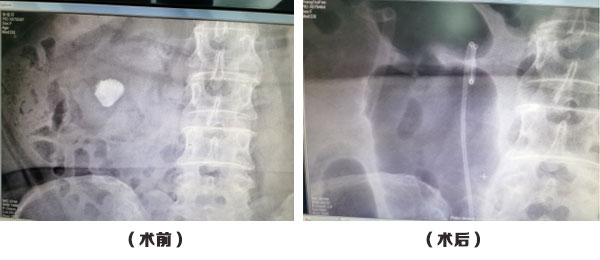

圖為PowerSuite正式落戶于醫(yī)院的第一天,李世江主任開展的首例PCNL術(shù)

患者情況:女,67歲,右腎結(jié)石(2.2cm),既往有右腎萎縮、肥胖,高血壓等多種復(fù)雜性疾病。由于患者身體基礎(chǔ)狀況差,合并疾病較多,手術(shù)治療十分棘手。遂邀請省級專家會(huì)診,擬定手術(shù)方案,最終制定了經(jīng)皮腎鏡鈥激光碎石術(shù)治療方案。

該手術(shù)碎石僅僅用了15分鐘就完成了碎石過程,“科醫(yī)人PowerSuite鈥激光手術(shù)系統(tǒng)”采用了世界首創(chuàng)智能合并激光管技術(shù)--4根激光管,強(qiáng)大的激光輸出頻率爆破及碎石粉末化功能,可以大大縮短碎石手術(shù)時(shí)間,也極大地減輕患者痛苦。術(shù)后復(fù)查未見殘留結(jié)石。